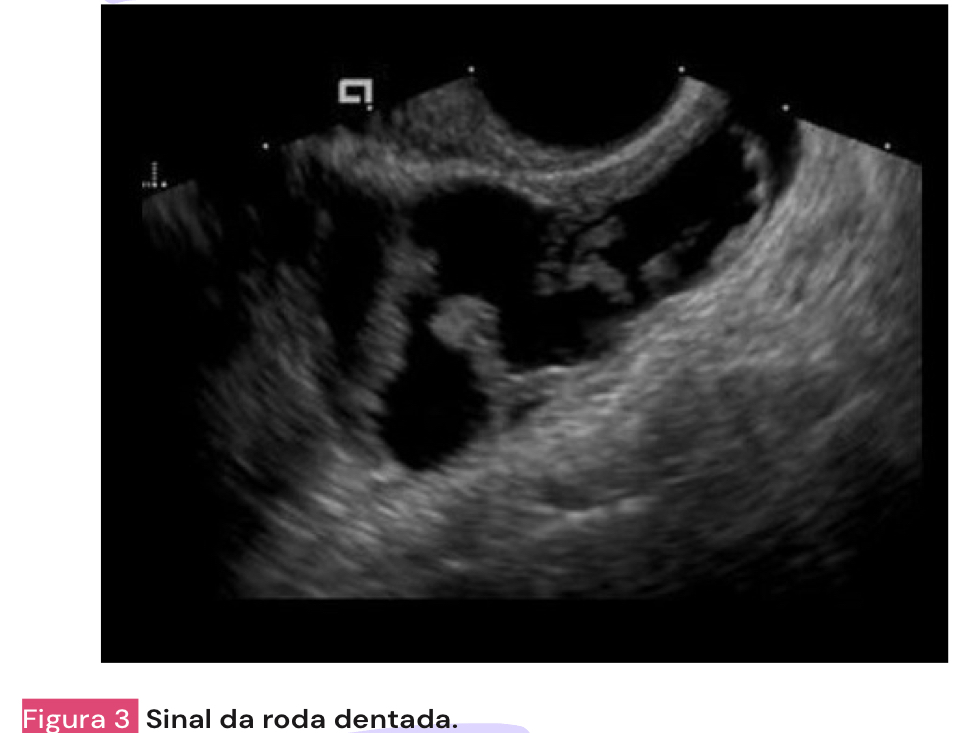

O que mais pode ser visto nos exames de imagem de uma paciente com DIPA?

A

• parede tubária espessa (>5mm)

• acumulo de liquido nas tubas

• tubas dilatadas (SINAL DA RODA DENTEADA)

• septos intra-tubareos

• abscesso tubo-ovariano